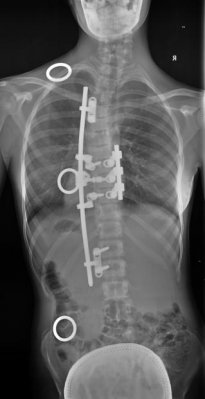

Nová metoda umožňuje nejen téměř dokonalé napravení deformity, ale současně zajišťuje i další přirozený růst obratlů a nabízí i unikátní techniku udržení pohyblivosti operované páteře. Nový typ instrumentace přináší maximální šetrnost ke tkáním operovaného dítěte a lepší výsledný kosmetický efekt. Velmi významným faktorem je i výrazné zvýšení bezpečnosti samotné operace, která vyžaduje méně implantovaného kovového materiálu.

Celkově nová metoda zajišťuje nápravu dětských skoliotických zakřivení páteře s výsledkem výrazně se blížícím neoperované rovné páteři.

Nová metoda operačního řešení dětských skolióz zajišťuje:

- vysokou účinnost napravení zakřivení

- růst páteře

- pohyb páteře

- 3D (trojdimenzionální) napravení zakřivení

- šetrnost k operovaným tkáním

- lepší výsledný kosmetický efekt

- bezpečnost operace